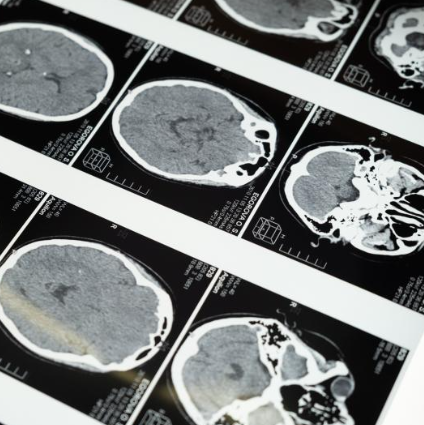

1. 치매 예방과 운동의 상관관계

치매는 단순한 노화가 아니라 뇌세포가 죽어가는 질병입니다.

기억력 저하, 판단력 상실, 성격 변화까지… 삶의 질을 파괴하죠.

하지만 반가운 사실도 있습니다. 규칙적인 운동만으로도 치매 예방이 가능하다는 점입니다!

운동은 단순히 몸만 단련하는 것이 아니라 뇌도 단련합니다.

특히 유산소 운동은 뇌 혈류를 증가시키고, 인지 기능을 유지시켜주는 뇌유래신경영양인자(BDNF)를 활성화합니다.